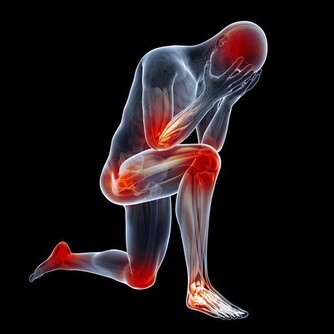

慢性型早期會出現煩躁、食慾減退、低熱、多汗、脫髮、以後有典型的骨痛症狀。

維生素D在所有維生素中是最容易使人中毒的一種,其中毒症狀和體徵主要有:高鈣血、肌無力、感情淡漠、頭痛、厭食、噁心、嘔吐、骨痛、異位性鈣化、蛋白尿、高血壓和心律失常等。慢性高鈣血可導致全身血管鈣化、腎臟鈣質沉著和迅速出現腎功能衰退。